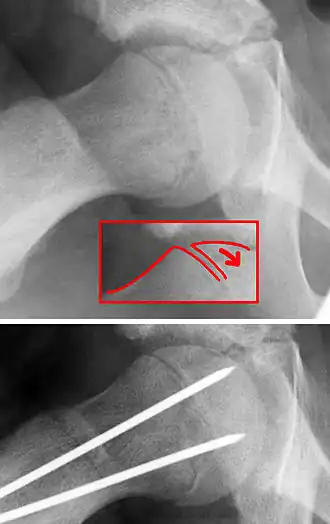

C'est le glissement en arrière et en bas de l'épiphyse proximale du fémur par rapport à la métaphyse. Ce glissement passe dans la zone hypertrophique du cartilage de conjugaison.

Sur le plan anatomique articulaire, les rapports de l'épiphyse et de sa surface articulaire (tête du fémur) avec l'acétabulum ne sont pas modifiés. Ce glissement est mieux compris en tant que glissement vers le haut et en avant de la métaphyse proximale du fémur (col) par rapport à l'épiphyse. Familiarisé avec cette manière de voir, le chirurgien visualise mieux les techniques opératoires.

- ostéosynthèse,

- épiphysiodèse,

- ostéotomie fémorale proximale,

- contention par grand plâtre pelvi-pédieux.